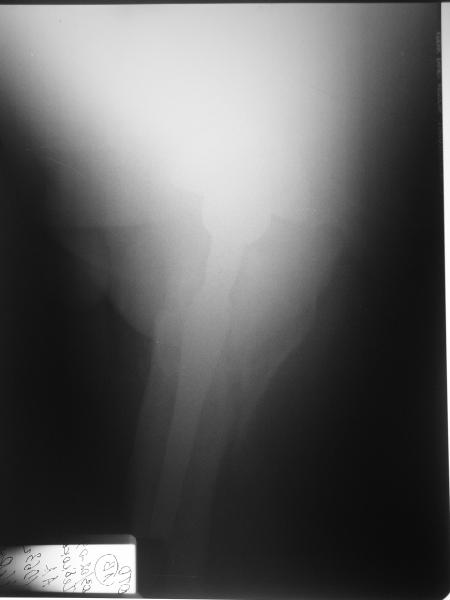

Перипротезный перелом бедра

Мужчине 1963 г.р. в октябре прошлого года в Кургане сделано эндопротезирование правого тазобедренного сустава (последствия перелома шейки бедра) бесцементным протезом Cerafit.

Все было благополучно, пациент уже ходил без трости, когда в начале января 2009 упал на улице на правый бок.

Госпиталирован по месту жительства (МСЧ г. Новоуральск). Уложен на скелетное вытяжение. На снимках от 3 февраля видно миграцию ножки в дистальном направлении, она явно нестабильна. В нашей больнице вряд ли что-то удастся сделать. Сопутствующих заболеваний нет. Хотелось бы получить совет по тактике. Если нужно ревизионное протезирование, куда лучше пациента направить? Спасибо.